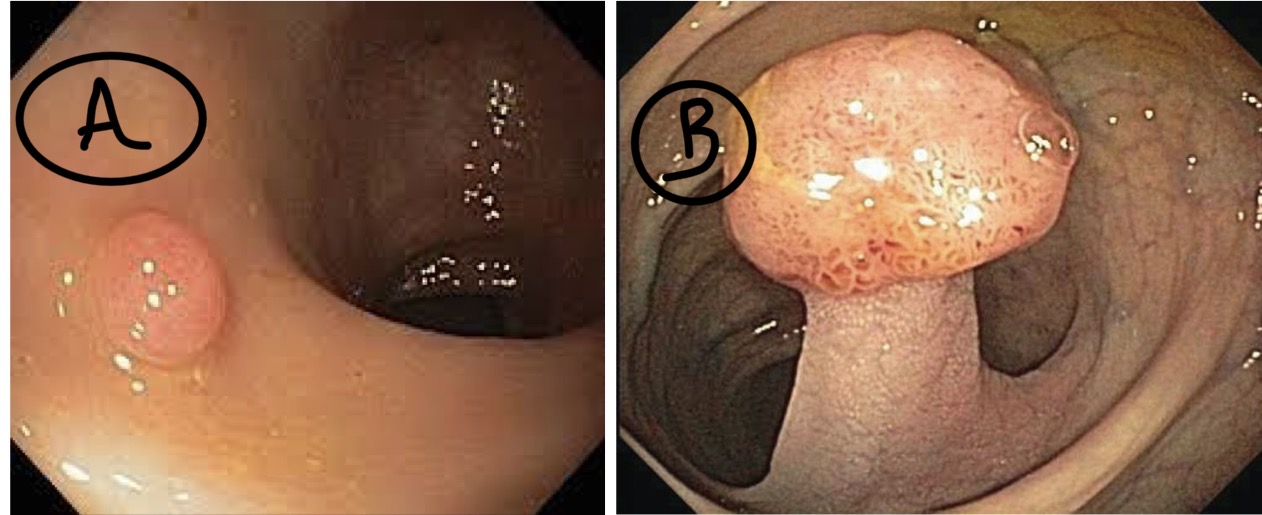

A- identify

B- describe

C- originate from ?

A- Colonic adenoma

B- (A) Sessile(dome shaped) colonic polyp (B) Pedunculated(stalked) colonic polyp

C- from benign epithelial tissue